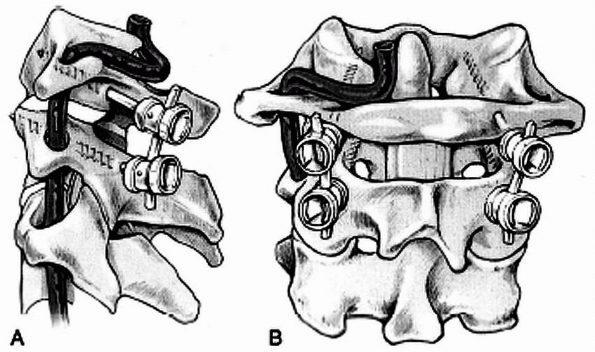

segmental wire has the advantage of achieving immediate stability of

the occipitocervical junction (Fig. 18-27), which allows the patient to be immobilized in a cervical collar after surgery, avoiding the need for halo immobilization.

upper cervical vertebrae are approached through a longitudinal midline

incision, which extends deep within the relatively avascular

intermuscular septum. The entire field is exposed subperiosteally. A

template of the intended shape of the stainless steel rod is made with

the appropriate length of Luque wire. Two burr holes are made on each

side, about 2 cm lateral to the midline and 2.5 cm above the foramen

magnum. Care should be taken to avoid the transverse and sigmoid sinus

when making these burr holes. At least 10 mm of intact cortical bone

should be left between the burr holes to ensure solid fixation. Luque

wires or Songer cables are passed in an extradural plane through the

two burr holes on each side of the midline. The wires or cables are

passed sublaminar in the upper cervical spine. The rod is bent to match

the template; this usually will have a head-neck angle of about 135

degrees and slight cervical lordosis. A Bend Meister (Sofamor/Danek,

Memphis, TN) may be helpful in bending the rod. The wires or cables are

secured to the rod. The spine and occiput are decorticated, and

autogenous cancellous bone grafting is performed.